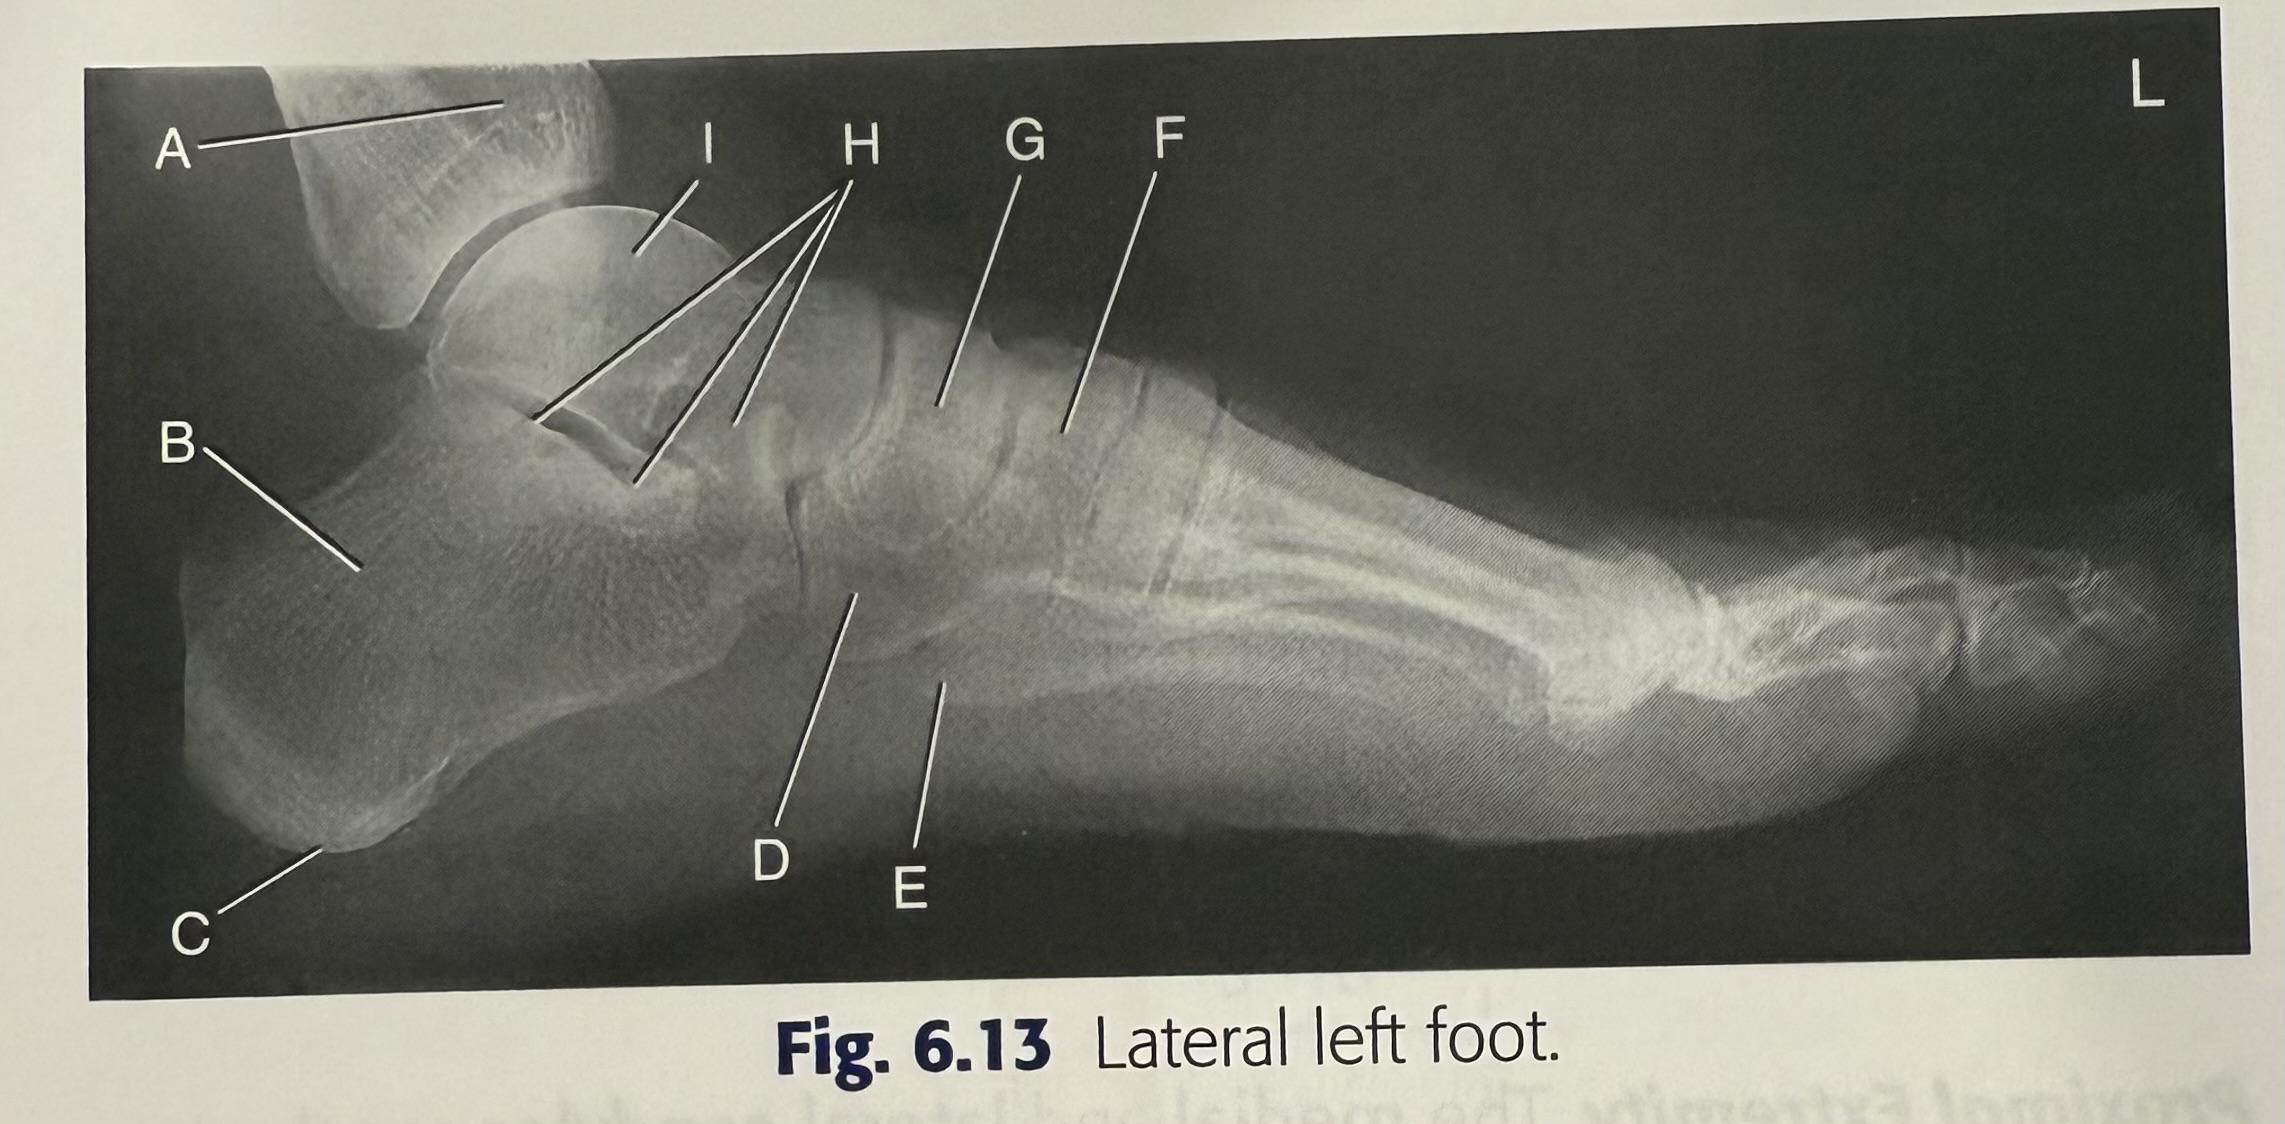

<p>A</p>

A

tibia

New cards

<p>B</p>

B

calcaneus

87

<p>C</p>

C

tuberosity of calcaneus

88

<p>D</p>

D

cuboid

89

<p>E</p>

E

5th metatarsal tuberosity

90

<p>F</p>

F

superimposed cuneiforms

91

<p>G</p>

G

navicular

92

<p>H</p>

H

subtalar joint

93

<p>I</p>

I

talus